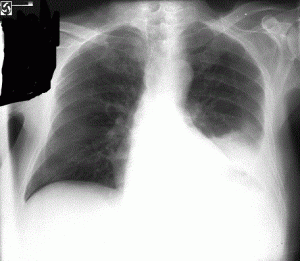

328) A 66 year old man is seen in your office for progressive shortness of breath on exertion for the past one year. He also reports dry cough. He denies any fever, hemoptysis or weight loss. He has no history of infections. He denies smoking. He has no other medical problems and has never been hospitalized. On examination, he is afebrile, blood pressure 120/80 mm Hg, RR 18/min and Pulse 82/min. There are no palpable chest-wall masses or lymphadenopathy. On auscultation, crackles are heard all over the lung fields, more pronounced at lung bases. Extremities show mild digital clubbing.

A chest x-ray is shown below:

Which of the following is expected to be seen with this disease?

A) Young age at onset

B) Rapid progression

C) High Resolution CT scans showing ill-defined cysts and pleural plaques

D) Poor or no response to steroids

E) Obstructive pattern on Pulmonary function tests

Filed under: Uncategorized, USMLE Test Prep | Tagged: Archer pulmonology, archer step 3 pulmonology, USMLE STEP 3 PULMONOLOGY, usmle-step-3-pulmoology | 16 Comments »